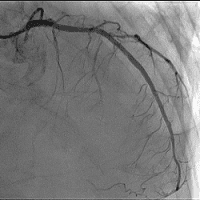

経皮的冠動脈インターベンションの一例

- 【1】術前

- 【2】ワイヤー通過

- 【3】ステント留置

- 【4】術後